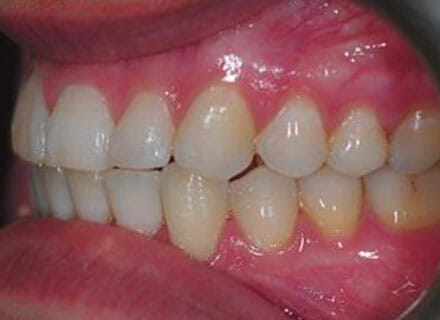

In this case the whole smile was affected by a tooth that was missing (a visible gap or hole at the side when smiling) and a tooth at the front that had grown the wrong side of the bite. We were able to correct the gap at the back by pulling the tooth behind forwards into the gap left by the previous extracted tooth. The clear brace also pushed the tooth at the front back in to the right position and the smile was massively improve. This case took around 18 months to complete.